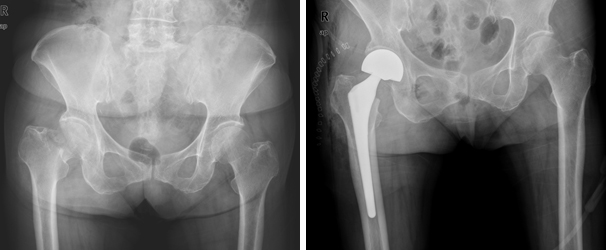

수술적 방법은 내고정술이 대원칙으로 되어 있으며, 수술적 내고정술에는 골절부위의 압박력을 얻어 골절부위의 골유합을 촉진할 수 있도록 고안된 활강 압박 고나사 고정술과 조기 체중부하가 가능한 골수강내 금속 고정술로 대별할 수 있으며, 인공 관절 치환술도 효과적인 치료 선택이 될 수 있습니다.

인공관절 반치환술 인공관절 반치환술 이미지